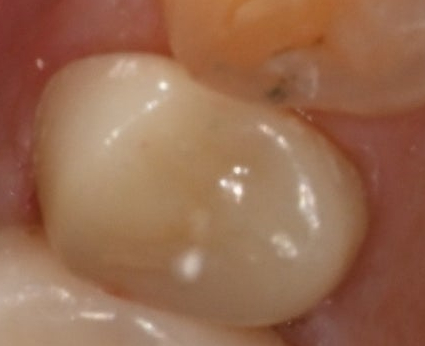

<치료 전 / 치료 후>

마지막은 지르코니아 크라운으로 단단하게 마무리

신경치료까지 끝나면 마지막은

지르코니아 크라운으로 마무리합니다.

지르코니아는 강도가 높고

오래가고, 잘 깨지지 않고

색도 자연스러워,

어금니에 정말 잘 맞는 재료예요.

이렇게 크라운까지 씌우면

어금니가 깨졌을 때에도

기능을 거의 원래처럼 회복할 수 있어요.